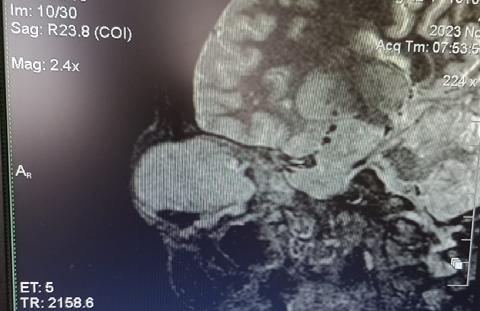

Se indica realización de TAC de órbita. Se realiza interconsulta con el Servicio de cabeza y cuello que decide cirugía de exenteración de contenido orbitario y envía de muestra a anatomía patológica.

La Tac de órbita informa tumoración en región orbitaria derecha. En tanto, los resultados del informe anatomopatológico indican:

• Tomografía de cerebro: informa enucleación ocular derecha, resto dentro de los parámetros normales.